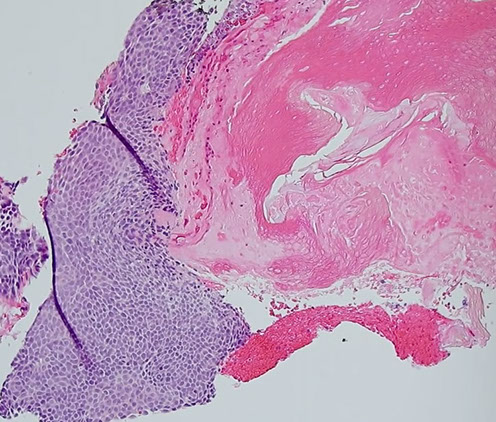

Desmoplastic trichoepithelioma

Presents as a firm donut on the cheeks of younger females with a central umbilicated nodule (dell)

Micro: tadpole-shaped islands (paisley-tie) c eosinophilic desmoplastic stroma

- calcifications and horn cysts common

- clefting only seen within stroma

- lymph aggs, apoptotic bodies and mits are rare

- no retraction space

- papillary mesenchymal bodies

IHC: scattered CK20+ Merkel cells

- not as many CK20+ cells as in Merkel cell carcinoma